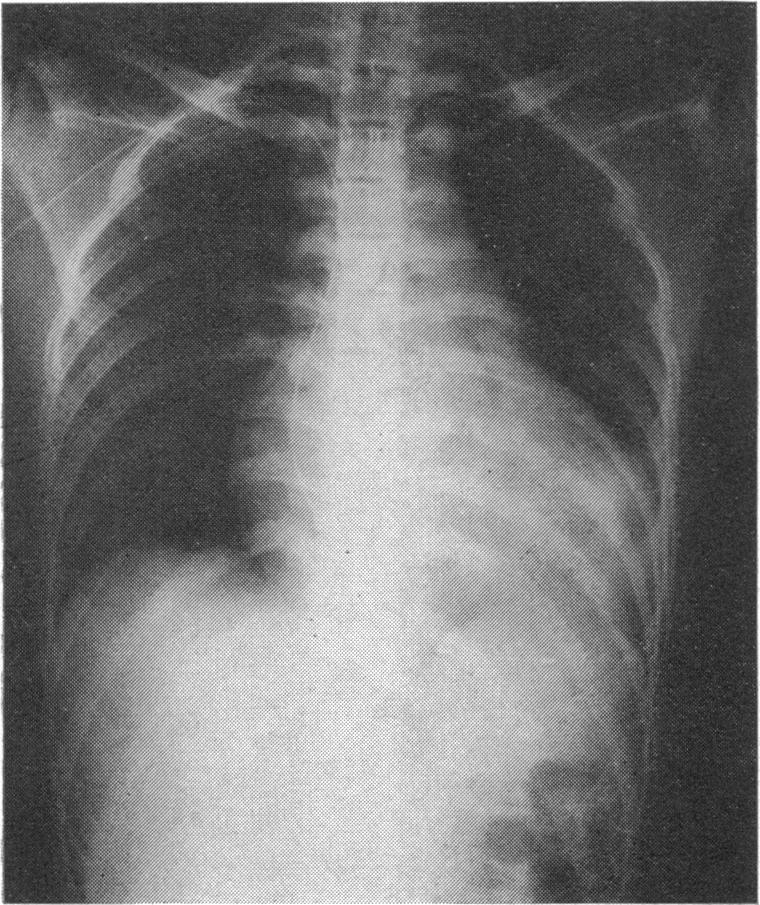

The sick sinus syndrome. A study of 15 cases.

Br Heart J. 1972 Sep;34(9):942-52. doi: 10.1136/hrt.34.9.942.